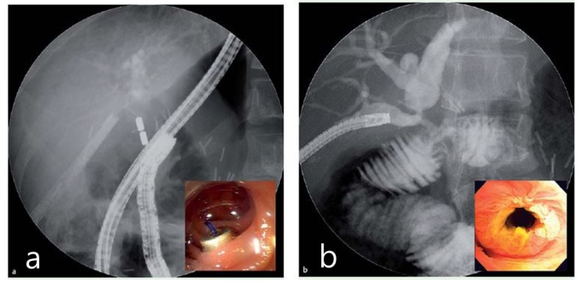

그림 1. 담도장관 협착 환자에게 적용하는 자기압축문합 과정을 보여주는 담관 x-ray 사진.

a. 자석은 대장 내시경시 용종을 제거하는 올가미를 사용하여 부착하며 다른 자석은 경피경간 담도 배액술(PTBD)에 의해 확보된 요로를 통해 이동시켜 두 자석이 서로 영향을 주도록 만든다.

b. 내주 경피경간의 담도경(PTCS) 카테터를 제거하면 문합부 개통을 확인할 수 있다.